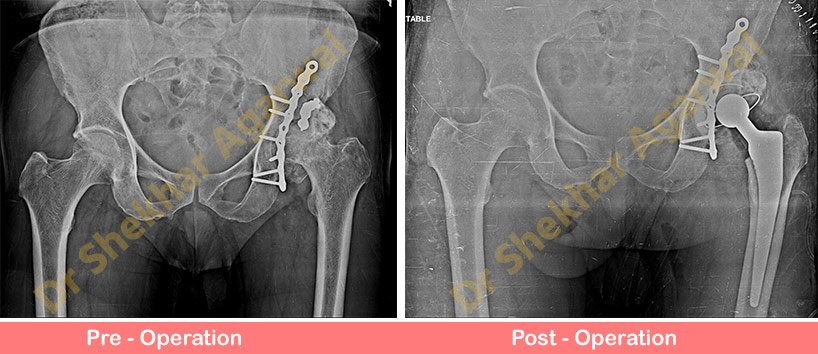

DITO is offering Best Hip Replacement Surgery in Delhi Affordable Cost. They provide ultimate goal of hip replacement surgery is pain relief and improved function.

Report StoryDITO is offering Best Hip Replacement Surgery in Delhi Affordable Cost. They provide ultimate goal of hip replacement surgery is pain relief and improved function.